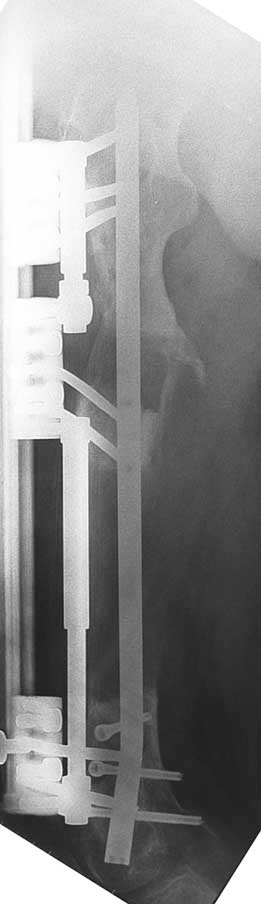

Uygun radikal debridman tüm nekrotik kemik ve yumuşak dokuların çıkartılmasını gerektirir, ve sıklıkla uzuvda instabiliteye neden olur. Kalan kemik ve yumuşak doku defektinin bir şekilde fiksasyonu ve rekonstrüksiyonu gereklidir. İlizarov’un ortaya koyduğu distraksiyon osteogenezi yöntemi, kaynamanın elde edilmesi, deformitenin düzeltilmesi, bacak boy eşitsizliğinin giderilmesi ve segmental defektlerin rekonstrükte edilmesi için başarıyla kullanılmaktadır.

Eksternal fiksatör ile geçen süre (eksternal fiksasyon indeksi), gereken distraksiyon miktarına bağlıdır ve bu süre boyunca bazı komplikasyonlarla karşılaşılabilir. Distraksiyon dönemi sona erdikten sonra, distraksiyon süresinin iki katını aşan konsolidasyon döneminde hastalar eksternal fiksatörü zorlukla tolere edebilirler. Yeterli konsolidasyon sağlanmadan eksternal fiksatör çıkartılırsa ise kırıklar, deformite ve kısalık oluşabilir. Hastanın fiksatör ile birlikte geçirdiği sürenin azaltılması ve böylece hasta konforunun ve aktivite düzeyinin arttırılması için intramedüller çivi üzerinden uzatma yöntemi uygulanmaktadır. Bu yöntemde distraksiyon dönemi sona erdiğinde kemiğin içindeki çivi statik olarak kilitlenmekte ve eksternal fiksatör çıkartılmaktadır. Stabilizasyon intramedüller çivi tarafından sağlandıktan sonra konsolidasyon dönemi gerçekleşmektedir. Bu şekilde hem eksternal fiksatörün uzun süre kalmasından hem de erken çıkartılmasından kaynaklanan komplikasyonların önüne geçilmektedir.

Vaka 1